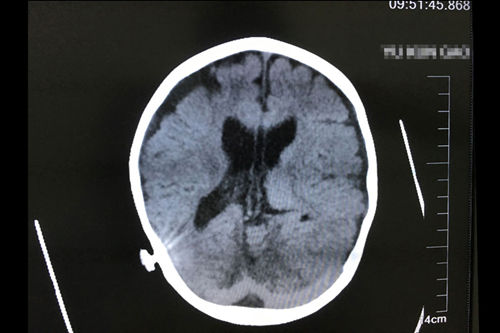

亮亮正式出院三个月后复查CT影像显示:慢性中度以上阻塞性脑积水,脑室分流术后改变